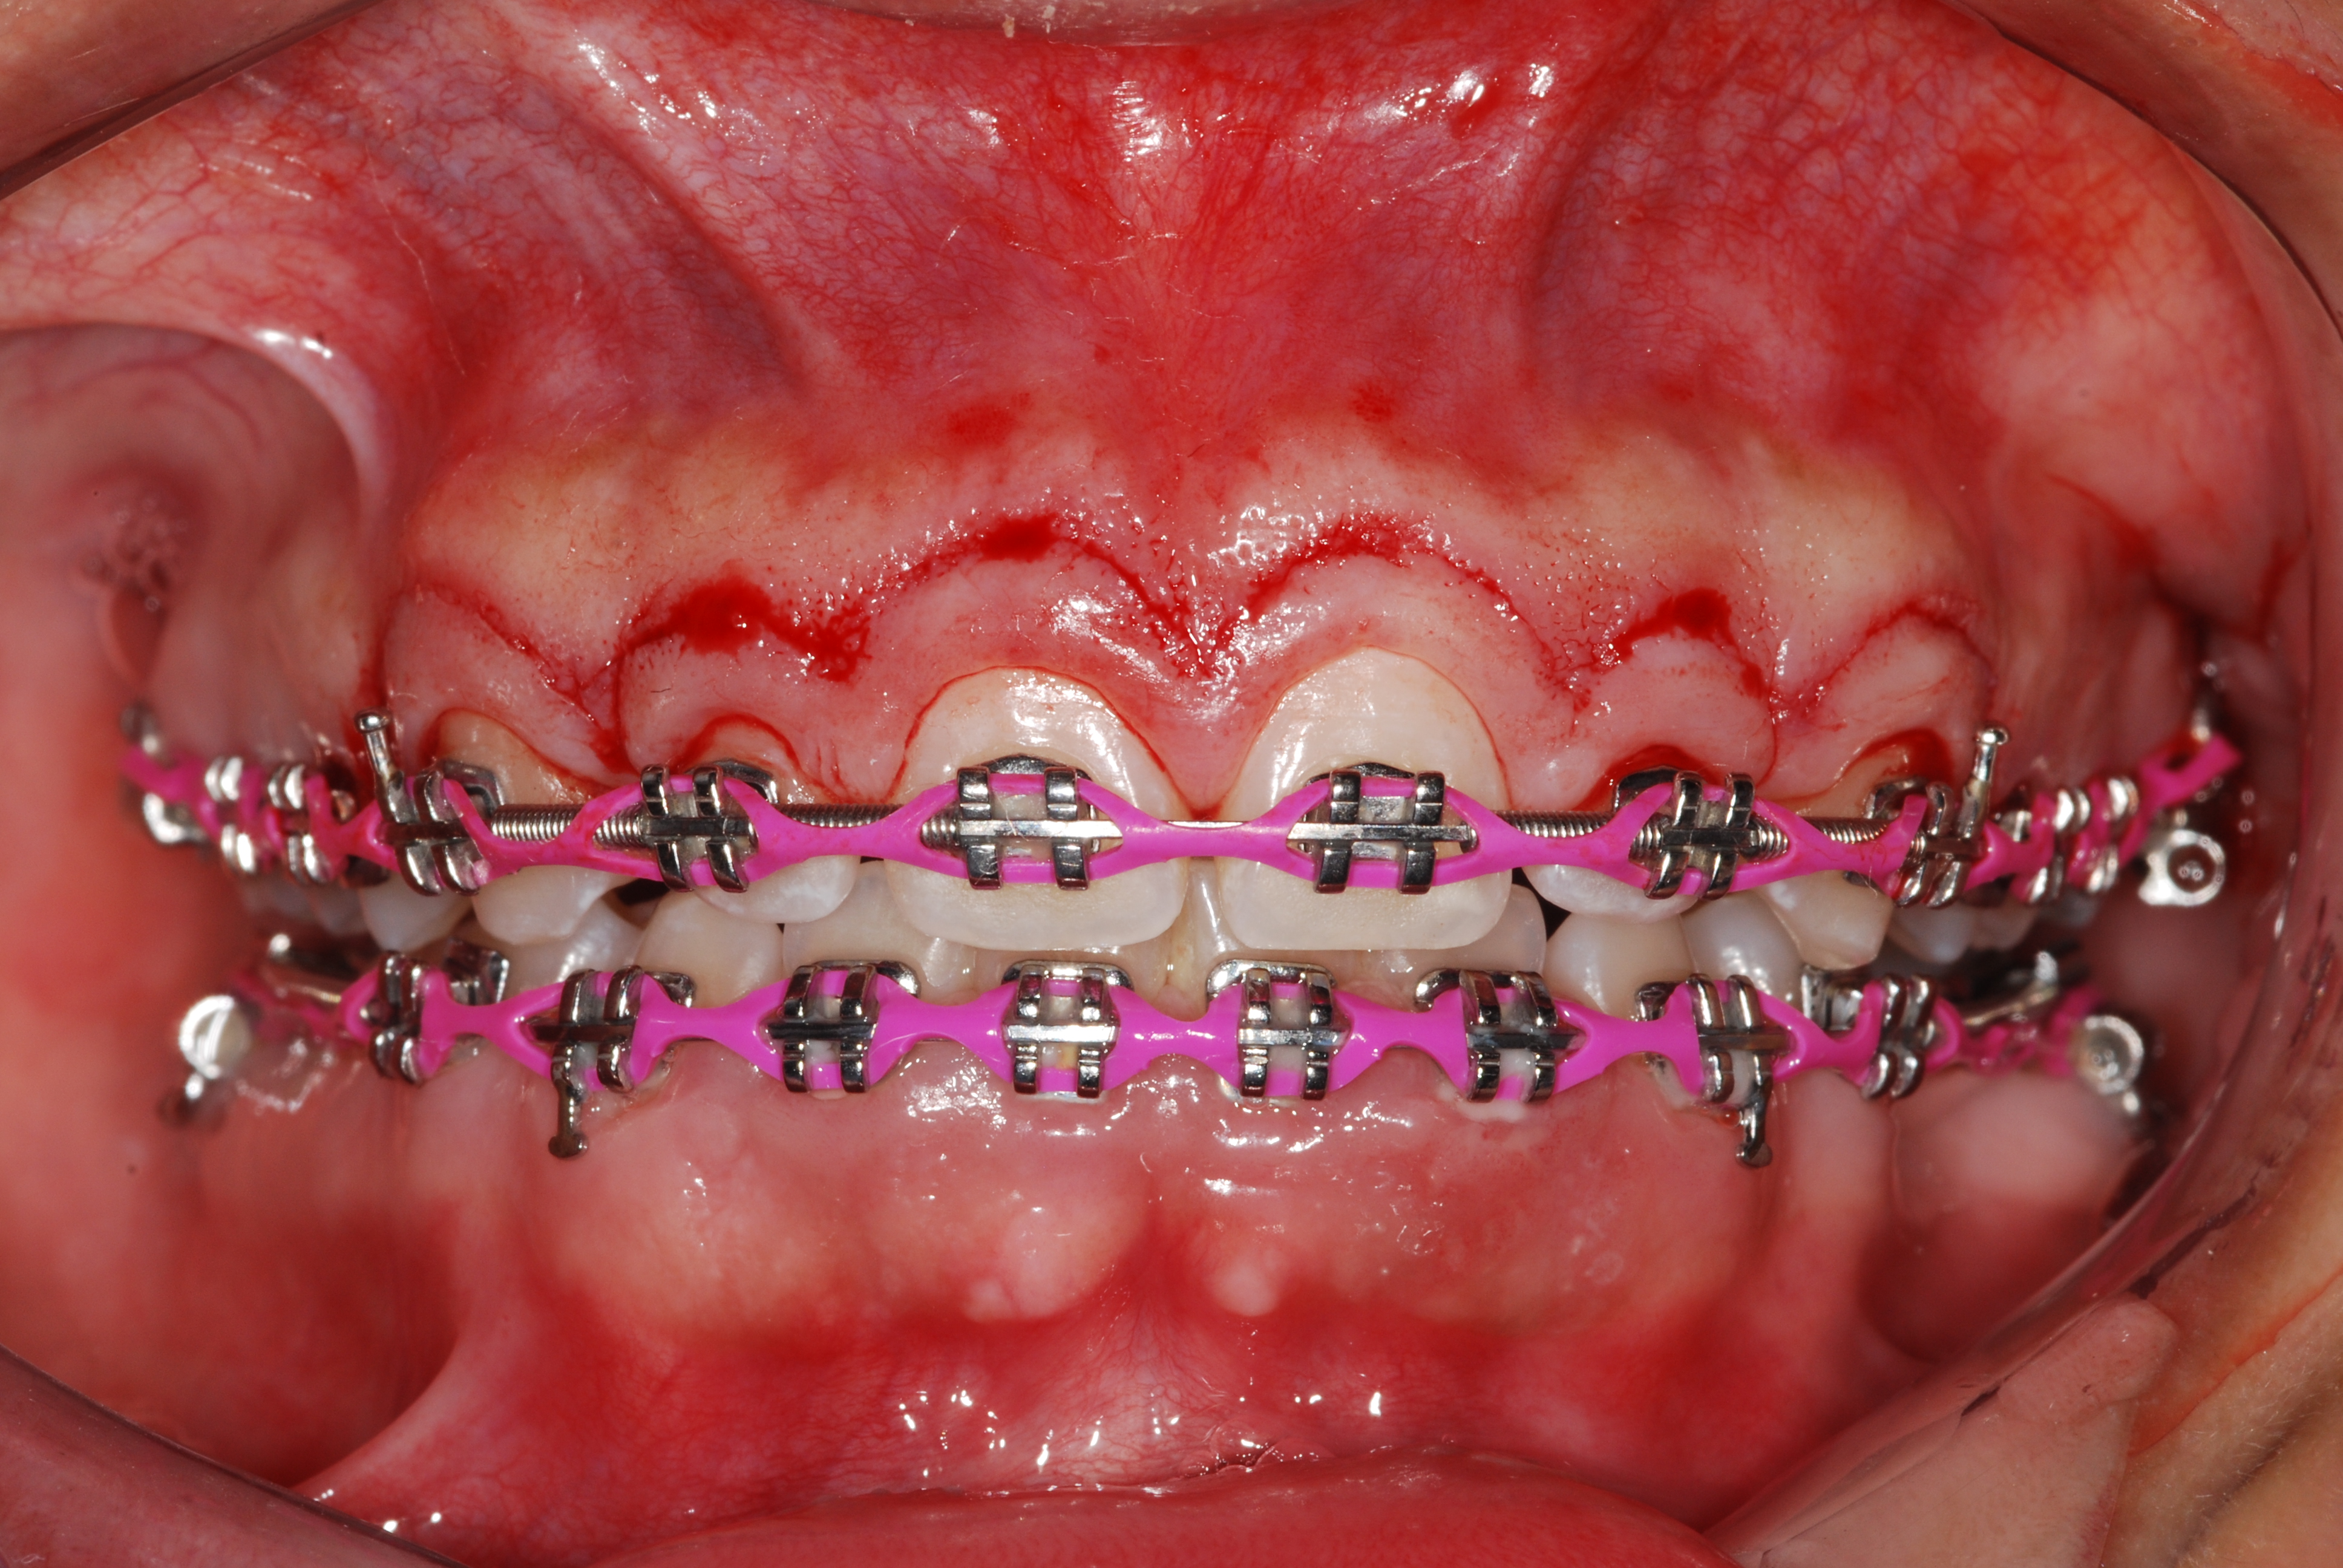

The presence of diastema, between anterior teeth, distorts a pleasing smile by concentrating the observer’s attention on the spaces. The patient’s needs and expectations must be considered in the process of treatment planning to ensure satisfaction with the treatment outcomes. There are many forms of therapy that can be used for diastema closure. A carefully developed diagnosis, which includes a determination of the causal elements and advanced treatment planning, allows the most appropriate treatment to be selected for each case. The aim of this paper is present a multidisciplinary approach as a solution to multiple diastemas in the anterior region using gingival tissue recontouring and direct adhesive restorations, with minimum wear of the dental structure, after the orthodontic intervention discussing the minimal intervention to obtain imperceptive and aesthetic final restoration. Thirty-six months after the treatment was carried out, the final aesthetic was maintained with all dental element details and gingival tissue harmony, without recurrence of periodontal pockets and the preservation of the tooth color and shape.